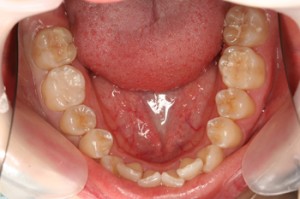

■口の中の金属を白くする症例

初診時

初診時(口を開いた状態)![]() |